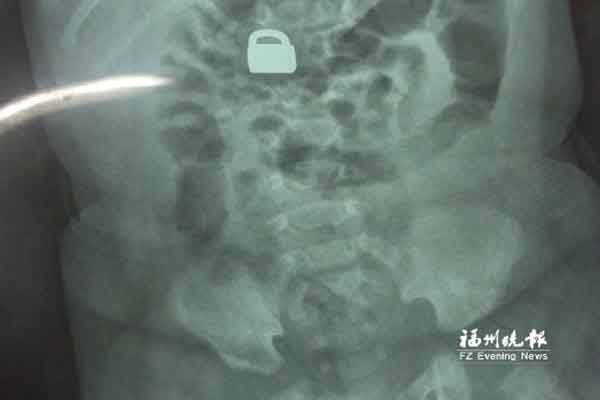

7.25龙岩当地医院拍的X光片显示,平安锁在宝宝体内

“X光片显示,那是一把1.5厘米×0.9厘米的平安锁,有指甲盖大小,已经到了宝宝的小肠处。”7月28日,陈惠萍见到宝宝时,吃了一惊,“他真的好小,被抱在妈妈怀里,眼睛微微睁开,我估计他的世界还是混沌的,没想到就已经接受了这么大的挑战。”